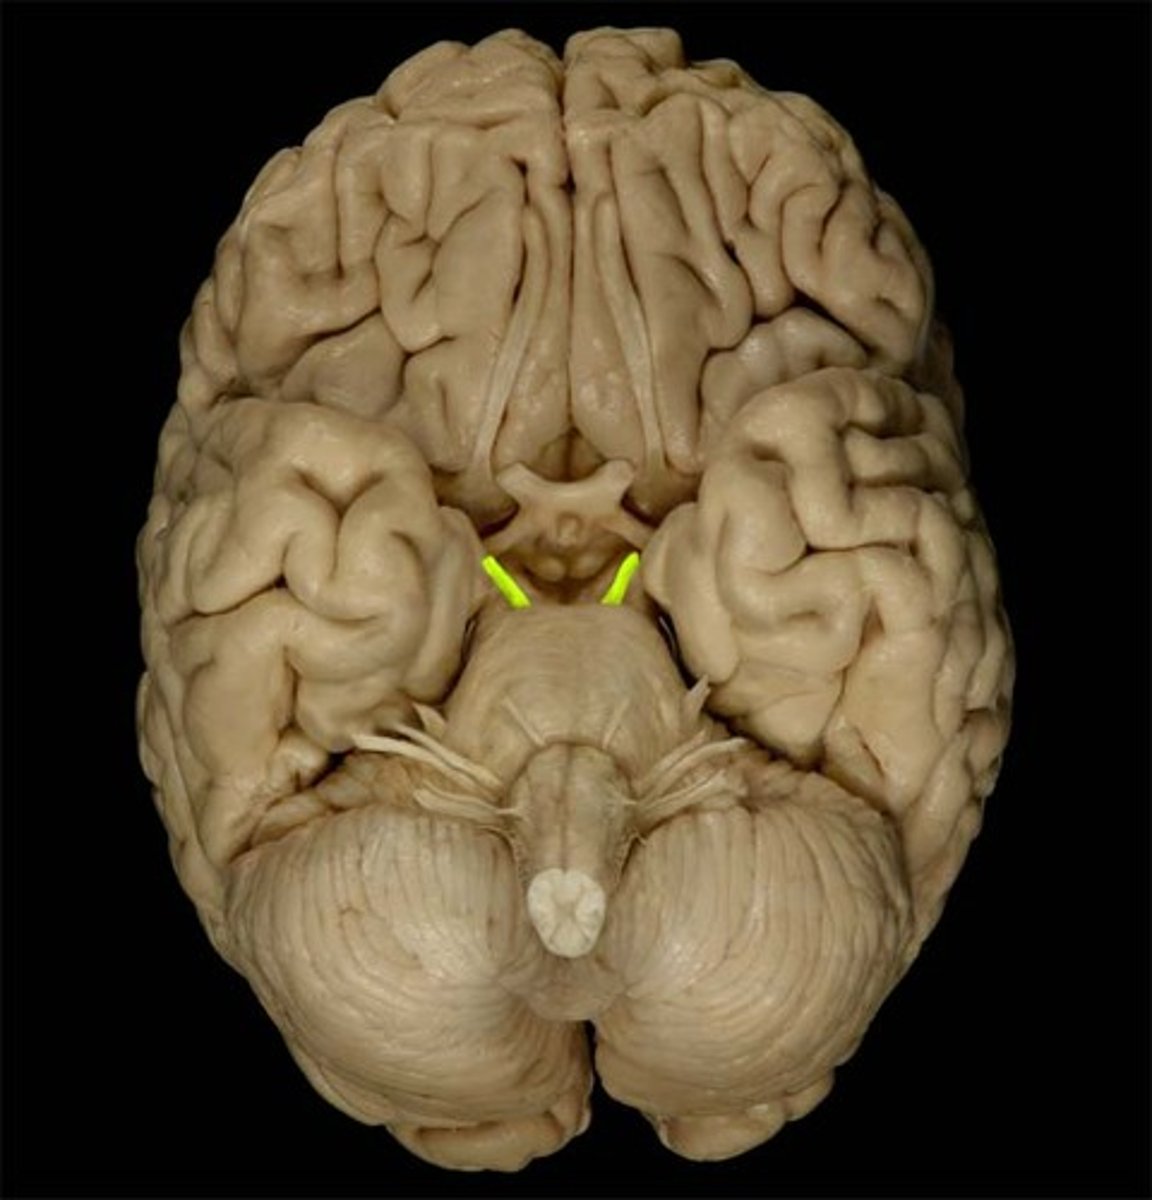

Oculomotor Nerve

Function: motor- eye movement; lid elevation, pupil contraction, lens shape

Location: Midbrain

Trochlear Nerve

Function: motor- eye movement (downward and inward)